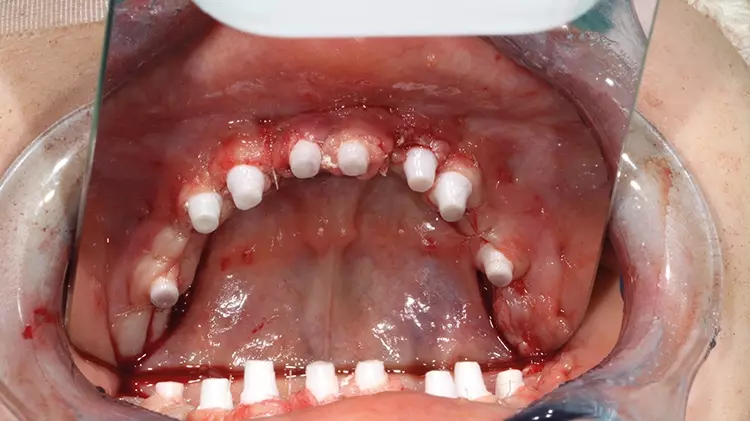

Abb. 13: Primärstabile, mittels schienenbasierter Navigation präzise inserierte SDS

Keramikimplantate im OK und UK in situ nach vollnavigierter Implantation mit

2ingis-Schienen. Alle einteiligen Implantate wurden direkt intraoperativ und intraoral

für die Langzeitprovisorien präpariert, die zweiteiligen wurden vorerst mit

einer Deckschraube verschlossen. SDS

Abb. 13: Primärstabile, mittels schienenbasierter Navigation präzise inserierte SDS Keramikimplantate im OK und UK in situ nach vollnavigierter Implantation mit 2ingis-Schienen. Alle einteiligen Implantate wurden direkt intraoperativ und intraoral für die Langzeitprovisorien präpariert, die zweiteiligen wurden vorerst mit einer Deckschraube verschlossen.

Die vollständige Sanierung mit den Keramikimplantaten SDS SWISS DENTAL SOLUTIONS wurde im vorliegenden Fall gemäß des SWISS BIOHEALTH ALL-IN-ONE CONCEPTS innerhalb einer Sitzung in Allgemeinnarkose durchgeführt (Abb. 13). Das für den Knochenstoffwechsel relevante Vitamin D kann nachweislich zusammen mit weiteren Mikronährstoffen, wie Vitamin K2, Magnesium etc., die Erfolgsquote der neutral, ohne Entzündungsprozess einheilenden Zirkonoxid-Keramik begünstigen [1-7]. Deshalb wurde zusätzlich zu weiteren vorbereitenden Maßnahmen im Rahmen eines operativen Begleitprotokolls (u.a. antibiotische Infusionen) auch der aktuelle Vitamin-D3-Wert erhoben, welcher nicht unter 70 ng/ml perioperativ liegen sollte [8].

Es wurde zunächst im Oberkiefer quadrantenweise in den Leerkieferabschnitten mithilfe der gefertigten Navigationsschienen implantiert. Anschließend erfolgte die Extraktion der nicht-erhaltungswürdigen Zähne 12 bis 22 und anschließender Sofortimplantation. Aufgrund eines großflächigeren Knochendefekts regio 26 wurde zur zusätzlichen Stabilisierung das Implantat 26 mit dem BISS BONE IMPLANT STABILIZATION SYSTEM kombiniert und der Wundverschluss gemäß des OPEN HEALING PROTOCOLS nach Prof. Dr. mult. Shahram Ghanaati durchgeführt [9] (Abb. 14).